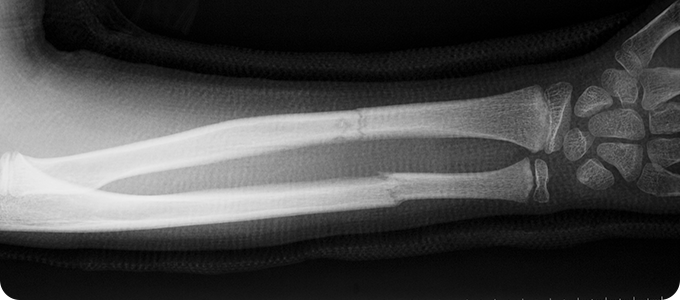

상지골절

• 위팔 골절, 쇄골 골절, 손목 골절은 손을 짚으면서 넘어질 때,

팔을 곧게 뻗은 채로 넘어질 때나, 교통사고, 타박 등에 의해 발생합니다.

골다공증 등으로 인해 뼈가 약해진 분에게 더 쉽게 발생할 수 있습니다.